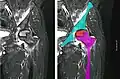

In the early stages, bone scintigraphy and MRI are the preferred diagnostic tools.[18][19]

Nuclear magnetic resonance of avascular necrosis of left femoral head. Man of 45 years with AIDS.